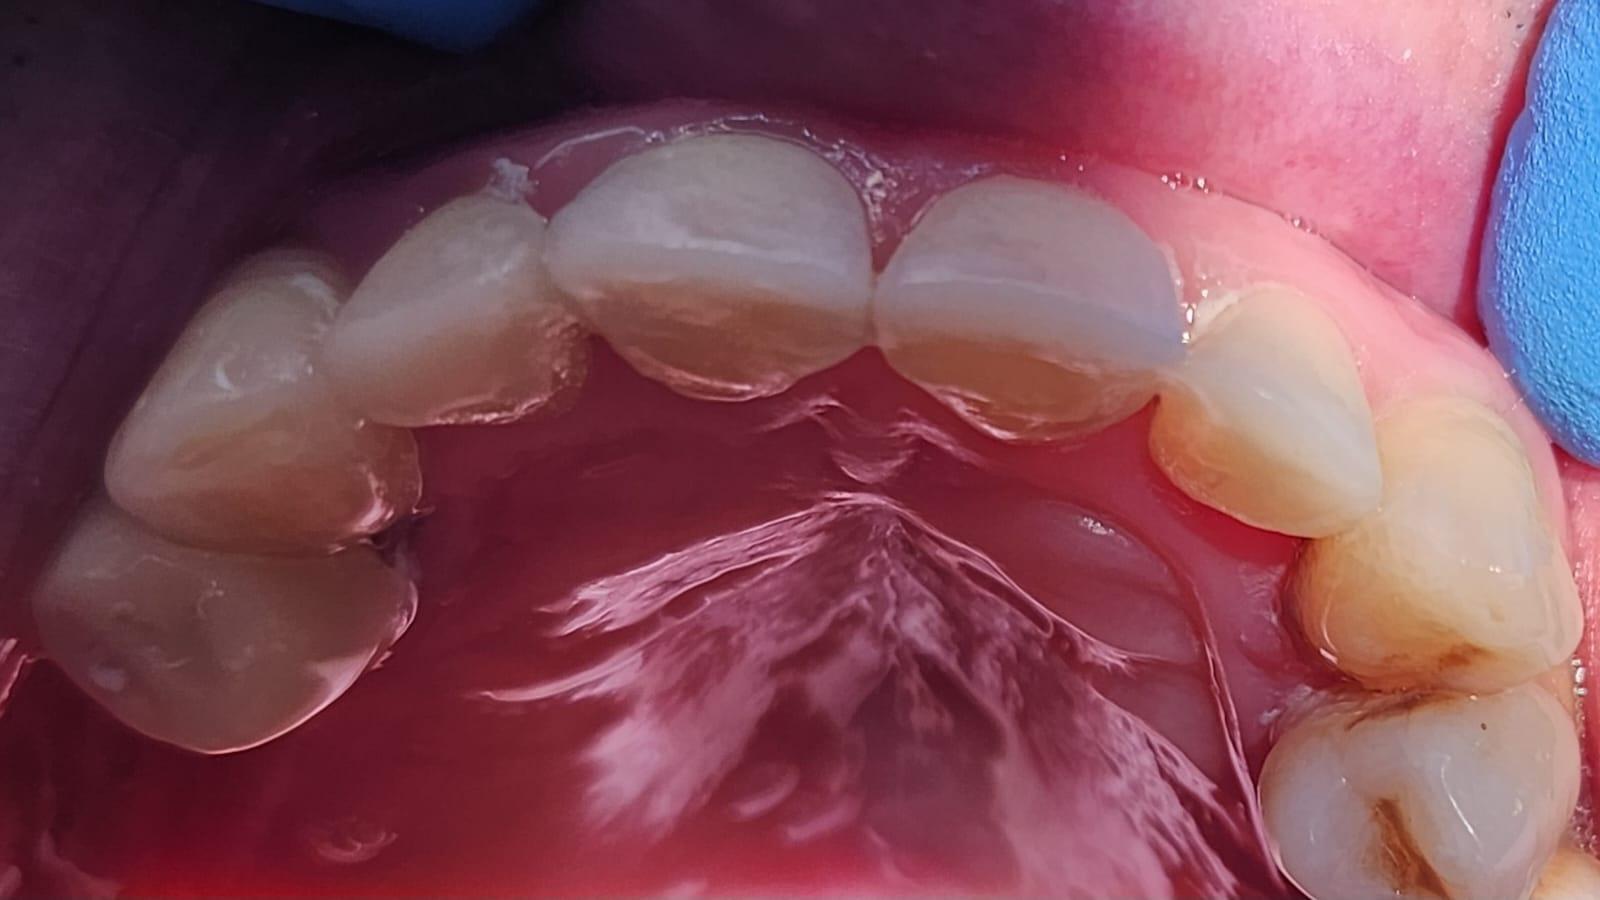

La Clinica LUY ESTHETIC ART se fac tratamente stomatologice pentru remedierea unui zambet perfect prin intermediul aparatului dentar. Pacientii au la dispozitie numeroase tipuri de aparate dentare, in functie de preferinte, necesitate si costuri. Pentru ca modificarile necesare sa se faca intr-un timp mai scurt, este necesara purtarea lui de la varste fragede, cand oasele nu sau dezvoltat complet.

Pot folosi aparate dentare si adultii, deoarece reprezinta cea mai buna varianta de indreptare a problemelor prezente la nivelul cavitatii orale, dar si de natura estetica. Medicul ortodont recomanda aparate dentare in urmatoarele cazuri: dinti strambi sau inghesuiti, dantura cu multe spatii, persoanele care au diastema (strungareata), dificultati la mestecarea alimentelor.

De cele mai multe ori este nevoie ca dispozitivele ortodontice sa fie purtate intre 6 – 24 luni. Aparatul dentar poate preveni aparitia gingivitei dar si cariile dentare. Dintii strambi si nealineati corespunzator sunt foarte greu de curatat. O igiena dentara incorecta duce la aparitia cariilor.